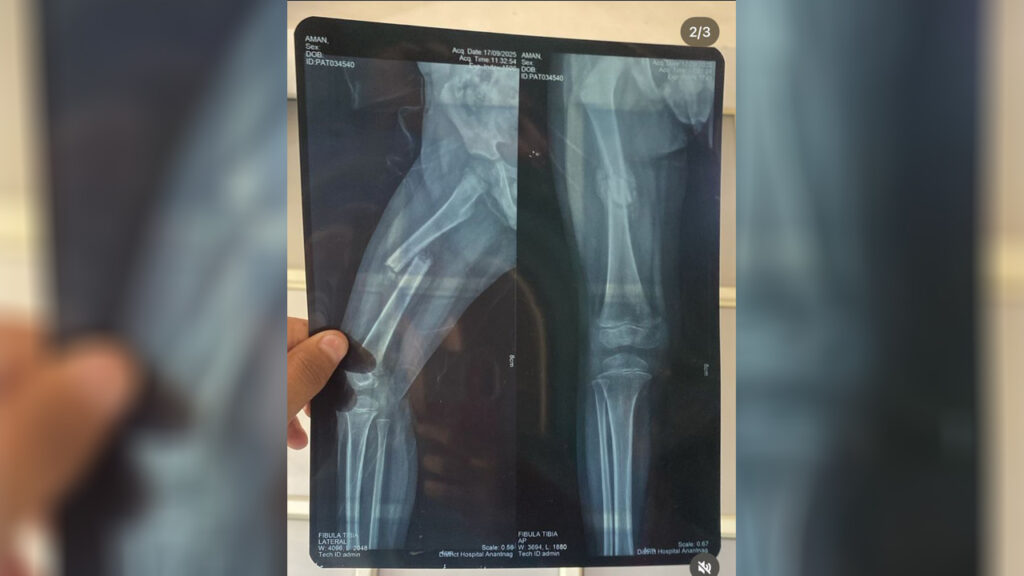

During the relief work our team came across a 5-year-old boy with a fractured leg, whose father had been unable to afford treatment while trying to provide for the family. The boy was brought to the medical camp by his mother, and the team immediately arranged for his transfer to Anantnag for surgery, covering all medical expenses to ensure he received urgent care.

This intervention highlights the critical need for support in remote villages affected by the recent landslides, and the team continues to provide assistance to the most vulnerable families.